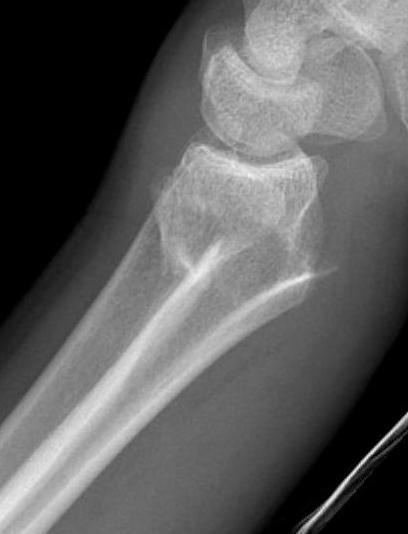

Dorsal ulna / volar ulna

Distal Radius Volar and Dorsal Ulna FragmentsDistal Radial Fracture CTDistal radius volar ulnar fracture

Distal Radius Dorsal Ulna FragmentDRUJ FractureDistal Radius Radioulna Fragments